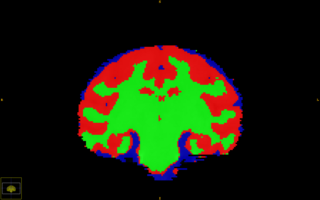

Subcortical Segmentation of Rhesus subject